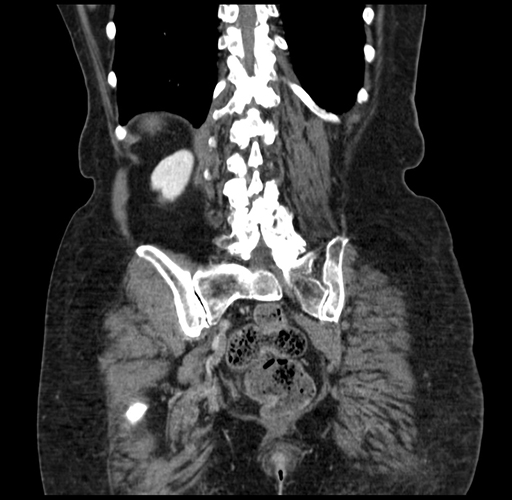

Coronal Venous